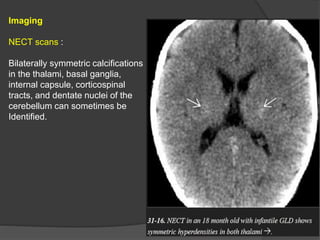

Imaging

NECT scans :

Bilaterally symmetric calcifications

in the thalami, basal ganglia,

internal capsule, corticospinal

tracts, and dentate nuclei of the

cerebellum can sometimes be

Identified.